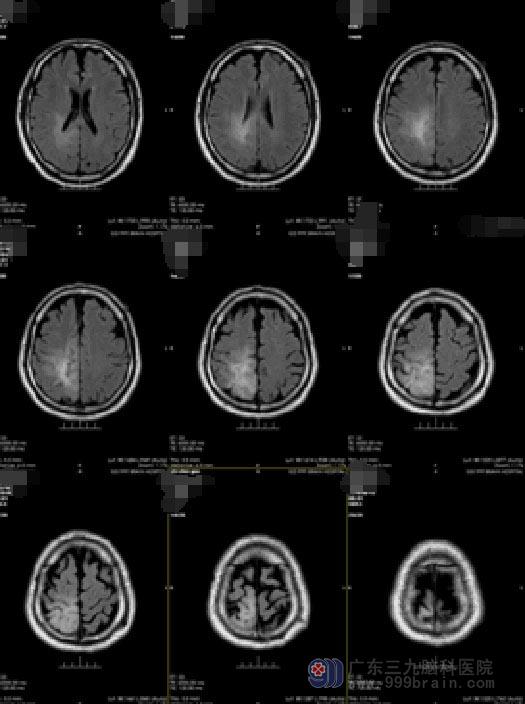

鲁明副院长主刀在唤醒麻醉下行右侧顶叶肿瘤切除术。手术中,利用导航准确地定位右侧顶叶的病变组织的位置,并在充分准备后唤醒患者完成医生要求的指定动作,利用电生理检测运动中枢,避开上下肢体运动中枢,显微镜下完整地切除肿瘤。手术过程顺利,患者肢体活动良好,待继续康复后出院。

手术前